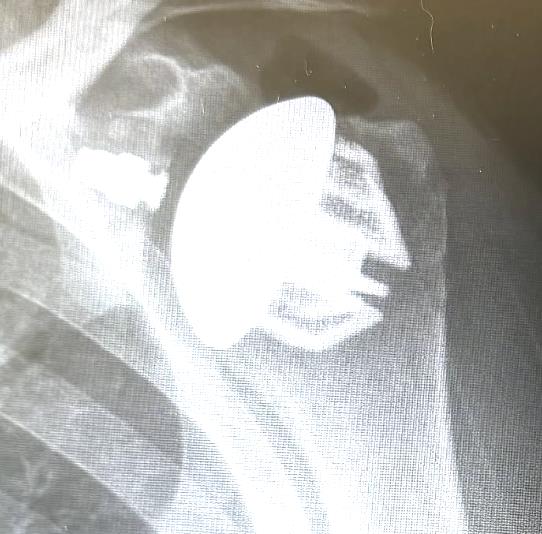

Summary The OsseoFit™ Stemless Shoulder System is indicated for anatomic total shoulder arthroplasty in patients where a bone-sparing, stemless solution is desired to maximize humeral fixation. It achieves this through OsseoTi® Porous Metal Technology and a site-specific fin design that creates a stable, biological press-fit while simplifying the surgical workflow with integrated suture holes. This system addresses a wide variety of patient anatomies using its versatile inlay and onlay size options. Indications Indications osteoarthritis indicated for anatomic total shoulder applications Contraindications local/systemic infection, sepsis, and osteomyelitis active local or systemic infection sepsis osteomyelitis inadequate humeral bone inadequate bone may lead to poor implant fixation large metaphyseal cysts may compromise stemless fixation irreparable cuff tear rotator cuff must be functionally reconstructable for anatomic total shoulder arthroplasty revision of any stemmed or stemless prothesis contraindicated for revision of any stemmed or stemless prosthesis Anatomy Osteology humeral head anatomic neck greater tuberosity lesser tuberosity bicipital groove metaphyseal cancellous bone Muscles deltoid forms the lateral border of the deltopectoral interval pectoralis major forms the medial border of the deltopectoral interval subscapularis released and repaired according to surgeon preference Ligaments glenohumeral capsule is released as needed to expose the humeral head and glenoid coracohumeral ligament contributes to rotator interval constraint superior, middle, and inferior glenohumeral ligaments contribute to anterior stability transverse humeral ligament overlies the bicipital groove Nerves axillary nerve courses inferior to the subscapularis and around the lateral humerus must be protected musculocutaneous nerve lies medial to the coracobrachialis and conjoint tendon suprascapular nerve is at risk with aggressive posterior-superior glenoid exposure Blood supply anterior and posterior humeral circumflex arteries arcuate artery is a terminal branch of the anterior humeral circumflex system suprascapular and circumflex scapular vessels Preoperative Planning X-rays A/P, scapular Y and axillary views evaluate bony anatomy, humeral head position, glenoid wear, deformity, and acquired bone loss use x-ray templates to estimate stemless humeral implant size assess whether an anatomic total shoulder reconstruction is appropriate CT assess bone quality and identify any humeral bone tissues use to assess bone quality and identify humeral bone issues that may affect implant selection evaluate metaphyseal bone stock, cysts, avascular necrosis, deformity, and cortical support Approach Extended deltopectoral anterior incision with an optional biceps tenodesis beginning immediately above the coracoid process and extending distally and laterally, following deltopectoral groove along the anterior border of the deltoid Technique Humeral head resection expose the humeral head and identify anatomic neck landmarks fixed-angle resection targets 135° inclination and 30° retroversion select left- or right-specific extramedullary resection guide align the guide post with the humeral shaft for fixed-angle resection align the 30° version rod with the forearm flexed at 90° place pins to define version and inclination and to stabilize the cutting surface resect the humeral head through the far side of the humeral head adjust the resection with the guide or calcar planer if needed assess bone quality with direct pressure perpendicular to the resected surface consider stemmed humeral fixation if cancellous bone is easily depressed or primary stability is questionable Humeral protection during glenoid preparation select the humeral resection cover that most closely fits the resected surface prepare the glenoid using the appropriate compatible glenoid technique remove the humeral resection cover before humeral sizing Humeral sizing place the humeral sizer onto the resection surface select the size intended to optimize cancellous bone fixation without violating the inner cortical rim orient the sizer so the bicipital groove bisects the superior and anterior fins insert the central Steinmann pin through the center of the sizer and through the lateral cortex avoid deep lateral cortical penetration to reduce risk to the axillary nerve place a lateral humeral retractor as needed to protect the axillary nerve confirm sizing after any additional planing Humeral bone preparation (boss reaming) ream until the boss reamer bottoms out on the resected surface ream over the central Steinmann pin with the boss reamer protect the lateral humerus and axillary nerve with a retractor remove the boss reamer while leaving the central Steinmann pin in place Humeral bone preparation (broaching) select the reference foot based on implant size select the broach that corresponds to the humeral sizer align the broach superior fin with the superior indicator line on the broach inserter slide the assembly over the central Steinmann pin until the broach contacts the resection surface remove the inserter-reference foot assembly and central Steinmann pin perform broach stability testing consider stemmed humeral fixation if the broach is unstable Humeral head trialing determine humeral head diameter and height using the humeral head sizing template or the resected humeral head seat the head trial assembly into the broach rotate the trial assembly with the hex driver to assess coverage of the resection surface confirm alignment with the anterior and posterior borders of the humeral resection increase offset if the head trial does not cover one side of the resection decrease offset if the head trial overhangs the resected bone reduce the joint and perform trial range of motion record the final offset letter or interval on the proximal humerus remove and disassemble the head trial assembly Implant insertion remove the broach with the slap hammer while maintaining an on-axis trajectory use the same reference foot size used for broach insertion select the implant size corresponding to the final broach and operative side slide the reference foot down until it uniformly contacts the resection surface confirm superior fin markings on reference foot, implant, and bone are aligned disengage the inserter-reference foot assembly with axial traction and slight rotational force as needed onlay implant center boss is slightly proud of the resection surface, with fin top surfaces flush inlay implant sits below the resection surface Humeral head implantation select the final humeral head implant matching the trial diameter and height use the offset letter or interval determined during trialing place the humeral head into the concave surface of the impactor base on a rigid sterile table impact the adapter into the humeral head with the disposable impactor using a mallet, strike the head impactor at least twice until the humeral head is flush with the resection visually confirm uniform seating consider implant subsidence and stemmed fixation if no pre-impaction gap is present Technical specifications Implant design anatomically shaped asymmetric anchor design designed to match natural asymmetric humeral anatomy designed to maximize cancellous bone fit and help avoid cortical impingement six-fin configuration with progressive tapered wedge design fins are designed for press-fit insertion each fin contains a fully porous window anterior suture holes are present for subscapularis repair Porous technology OsseoTi® Porous Metal Technology is used in the stemless implant porous architecture is designed to mimic human cancellous bone design incorporates a fully porous 3D printed OsseoTi® lattice within a titanium framework Technical specifications OsseoFit Onlay Anchor Implant Side Size Left 1, 2, 3, 4, 5 Right 1, 2, 3, 4, 5 OsseoFit Inlay Anchor Implant Side Size Left 1, 2, 3, 4, 5 Right 1, 2, 3, 4, 5 OsseoFit Humeral Head Adapter